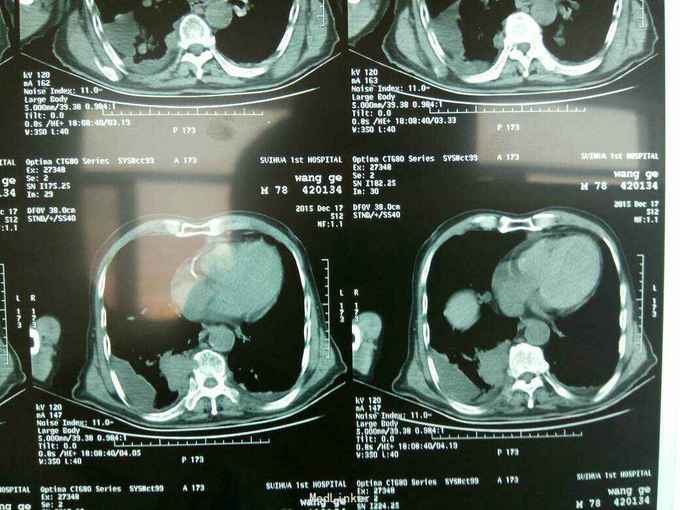

根据病史查体诊断:腰间盘突出症待确诊。应用消肿营养神经镇痛治疗。一天。查核磁共振示:腰椎多节段间盘突出伴椎管狭窄。第二腰椎骨破坏侵及椎板。部分突入椎管,脊髓受压。诊断:腰间盘突出伴椎管狭窄。第二腰椎转移癌,脊髓受压。经与家属沟通,查双肺CT:双肺下叶炎症。肺部纤维化。可见肿瘤阴影。肋骨及胸膜受累。胸椎部分骨破坏。最终诊断:双肺癌,胸椎,腰椎骨转移,脊髓受压。多节段腰椎间盘突出。病人至肿瘤科治疗。